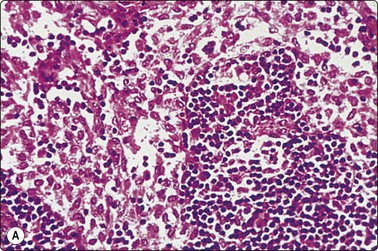

image

Fig. 5.4 Reactive lymphadenopathy, follicular

Tissue section showing detail of germinal center with centroblasts, centrocytes and tingible body macrophages. Outer rim of small lymphocytes. The corresponding cytological pattern is shown in Figure 5.5 (H&E, HP).

(Reproduced with permission from van Heerde et al.9)